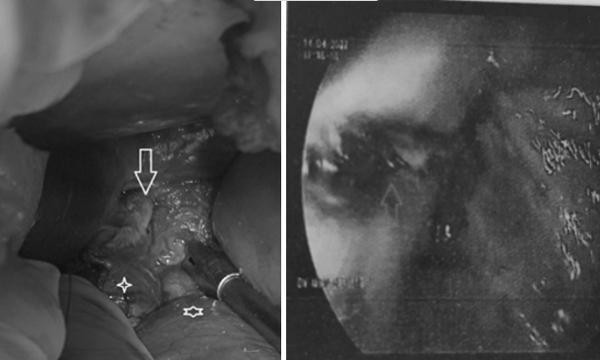

Hình ảnh thực quản trong nội soi dạ dày (bên phải) và lỗ thủng thực quản phát hiện khi phẫu thuật vùng bụng.

Kết quả thám sát vùng bụng thấy bụng bệnh nhân sạch nhưng quanh thực quản bụng và tâm vị bị bầm. Bơm chất chỉ thị màu, bác sĩ ghi nhận nam bệnh nhân có đường rách thực quản dài 3cm.

Bệnh nhân đã được phẫu thuật khâu lại lỗ thủng thực quản, đắp một phần mạc nối lớn lên đường khâu. Anh cũng được đặt thêm 2 ống dẫn lưu bên cạnh phải - trái thực quản bụng và được mở dạ dày nuôi ăn.